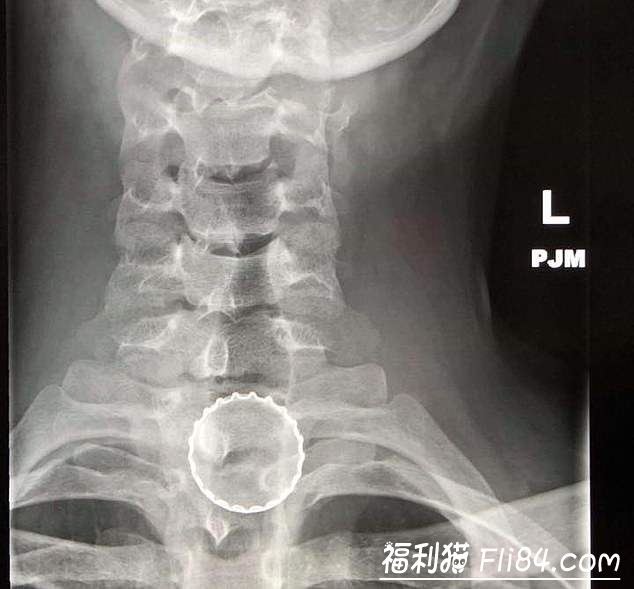

X光机下拍到的各种异物

喉咙・遥控器・保险套・坚果・激光笔・塑胶製的玩具剑・保险丝・冰淇淋盖子・助听器・胶囊・拼图・钥匙・钻头・口香糖・圣诞节装饰物